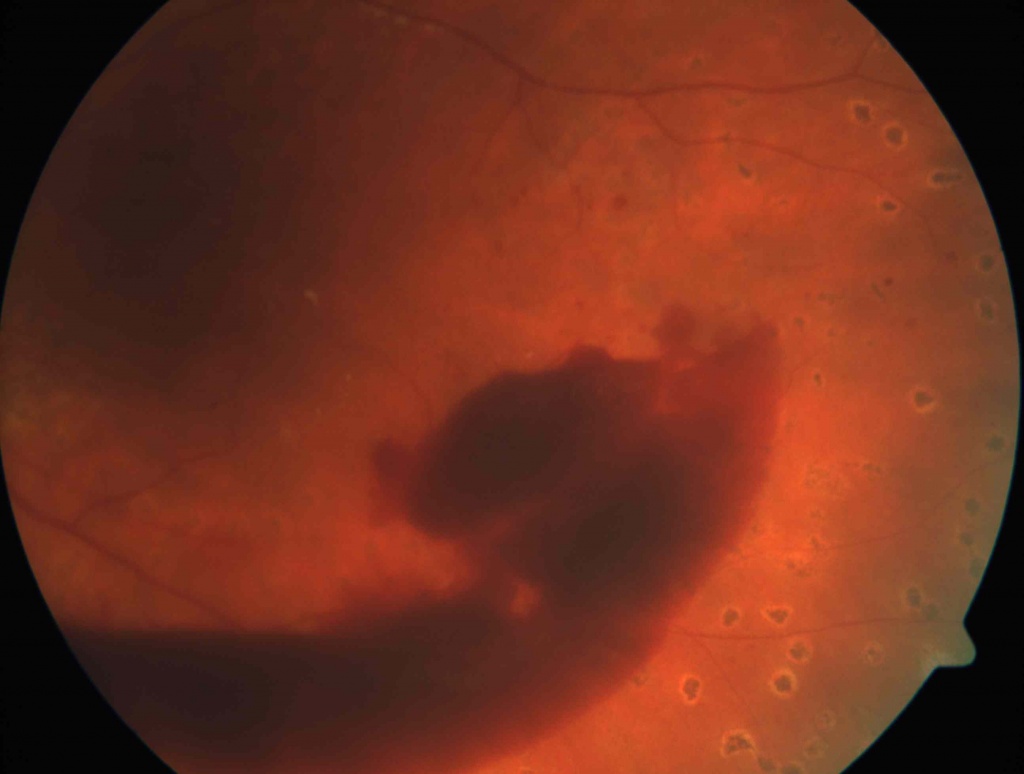

Гемофтальм -это кровоизлияние в стекловидное тело. Пациенты с гемофтальмом предъявляют жалобы на плавающие в поле зрения помутнения,«мушки», затуманивание зрения, появление паутины перед глазом. При тотальных гемофтальмах зрение снижается резко. Это может происходить при травмах, часто при сахарном диабете, гипертонии,заболеваниях крови, васкулитах. Иногда под гемофтальмом маскируется отслойка сетчатки. Частичные гемофтальмы могут рассасываться самостоятельно или при помощи рассасывающих препаратов. Тотальные кровоизлияния нуждаются в хирургическом лечении- витрэктомии. Любые кровоизлияния могут приводить к образованию спаек с сетчаткой и шварт, что в свою очередь вызывает отслойку сетчатки.

Отслойка сетчатки -патологическое состояние глаза,которое нуждается в срочном оперативном лечении, так как это заболевание приводит к достаточно быстрой полной потере зрения. Отслойки могут быть регматогенными- в результате образования разрыва сетчатки, как правило после трав и при близорукости; тракционными, возникающих после гемофтальмов и экссудативными при воспалительных заболеваниях и при опухолях сосудистой оболочки. Предвестниками отслойки сетчатки могут быть появление вспышек, искр, плавающих точек, что может указывать на образование разрыва сетчатки. Эти жалобы служат поводом для обращения к офтальмологу, так как на данном этапе возможно остановить развитие отслойки сетчатки при помощи лазеркоагуляции сетчатки. Далее появляются жалобы на снижение зрения и возникновение «занавески» перед глазом. Это признаки уже начавшейся отслойки сетчатки. Хирургическое лечение- единственный метод лечения при отслойке сетчатки. Витрэктомия - одно из самых сложных оперативных вмешательств в офтальмологии. Как правило, операции при отслойке сетчатки многоэтапные с применение вводимых в полость стекловидного тела перфтора и силиконового масла, одномоментной эндолазерлазеркоагуляцией. Реже выполняются эписклеральные операции.

Диабетическая ретинопатия – проявление сахарного диабета на глазном дне через 5-10 лет после заболевания. Диабетическая ретинопатия представляет собой поражение капилляров сосудов сетчатки на фоне гипергликемии в виде микрососудистых окклюзий и увеличением проницаемости сосудистой стенки и выходом жидкости в окружающие ткани. Клинически выделяют начальную-непролиферативную стадию (фоновую) диабетической ретинопатии, препролиферативную и наиболее тяжелую-пролиферативную, которая часто осложняется возникновением рецидивурующих кровоизлияний (гемофтальмов) в стекловидное тело. Нерассосавшиеся кровоизлияния могут приводить к развитию тракционной отслойки сетчатки. В начальных стадиях пациенты как правило жалоб не предъявляют. При прогрессировании процесса снижается зрение, появляются плавающие мошки и помутнения. Лечение диабетической ретинопатии начинают с лазеркоагуляции сетчатки, которая выполняется в несколько этапов. Лечение может сочетатся с введением в полость глаза лекарств- ингибиторов ангиогенеза. При гемофтальмах и отслойках сетчатки проводится оперативное лечение- витрэктомия.